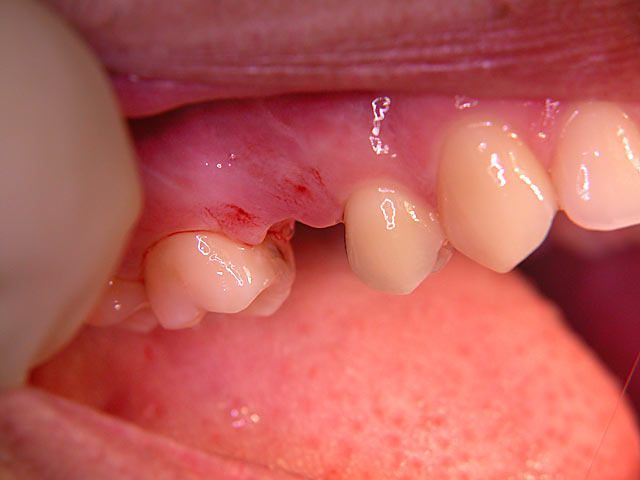

Kurzimplantate und Sofort – Implantate: